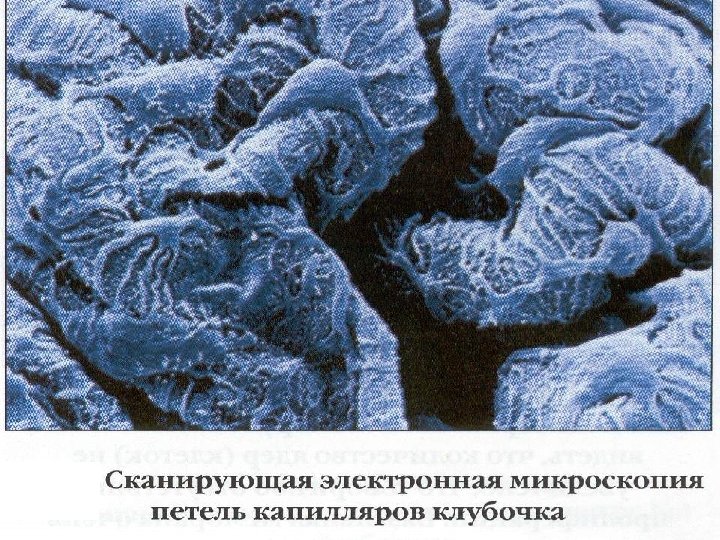

Эпителиальная клетка (подоцит) Отростки подоцита Базальная мембрана Эндотелиальная клетка Просвет капилляра Мезангиальная клетка Мезангиальный матрикс